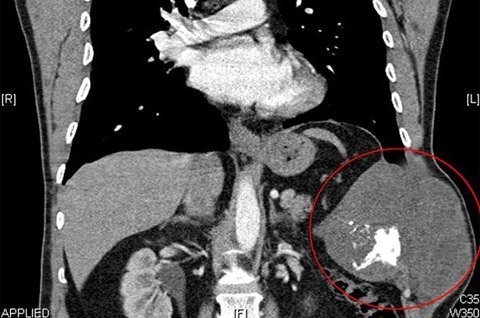

Ảnh chụp cho thấy khối u ung thư sụn ác tính (khoanh tròn) trong lồng ngực của Marek Barden. Ảnh: Carters

Cách đây khoảng 1 năm, anh Barden nhận thấy bên sườn của mình có một chỗ u lên nhưng lại phớt lờ nó vì nghĩ đó là hậu quả của tai nạn xe đạp. Tuy nhiên, kết quả chụp cắt lớp hồi tháng 8 năm ngoái hé lộ, anh có một khối u ung thư sụn ác tính (chondrasarcoma).